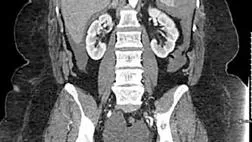

При поступлении в стационар у пациентки отмечена гипотония — АД 73/38 мм рт. ст., ЧСС 75 ударов в минуту, уровень гемоглобина составлял 101 г/л. При РКТ органов брюшной полости выявлена гематома в области селезенки размером до 4 см (рис. 1). Поскольку экстравазация отсутствовала, было принято решение о консервативной терапии. В ходе лечения отмечалось снижение уровня гемоглобина до 73 г/л, что потребовало гемотрансфузии. Через 7 суток пациентка была выписана из стационара.

image001.jpg

Рисунок 1 [1].